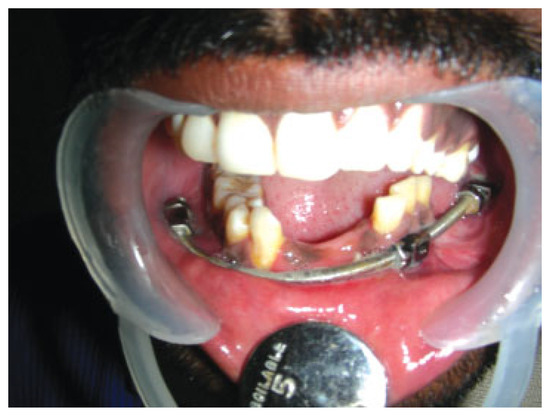

Mandibulo-maxillary fixation (MMF) screws are inserted into the bony base of both jaws in the process of fracture realignment and immobilisation. The screw heads act as anchor points to fasten wire loops or rubber bands connecting the mandible to the...